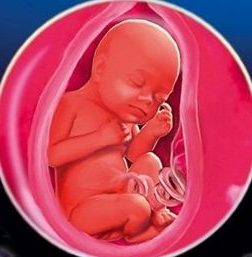

На певних етапах розвитку малюк, перебуваючи в животі, починає поступово ворушитися. Таких моментів з радістю чекає не тільки майбутня матуся, а й вся рідня: майбутній батько, бабуся, дідусь, брат або сестра. У багатьох випадках, батьки дуже переживають, якщо відчувають те, що дитина мало ворушиться. Щоб точно визначитися, чи дійсно пора турбуватися або ж нічого серйозного немає, необхідно трохи розібратися в особливостях внутрішньоутробного розвитку малюка.

Малюк може почати ворушитися в утробі матері набагато раніше, ніж вона це відчує. При очікуванні первістка, перші ворушіння вона може відчути на 20 тижні, в свою чергу ворушіння другої чи третьої дитини будуть помітні вже на 17 - 18 тижні. Коли термін добігає 24 - 32 тижні, майбутня матуся починає відчувати ворушіння своєї дитини ще частіше, ніж на початку вагітності. Це відбувається через швидке розвитку малюка і достатнього простору в матці. На більш пізніх термінах місця стає менше і, відповідно, дитина починає ворушитися менше. При цьому при наближенні термінів пологів, жінка починає відчувати все більший дискомфорт і болі при рухах свою дитину. Дане явище цілком нормально і боятися його не варто. Внутрішні органи стискаються, а шкіра натягується - від цього і виникають неприємні відчуття.

почалася 27 тиждень вагітності, це середина другої половини вагітності. Дитина вже став схожий на звичайного новонародженого і якщо він зараз народиться, шансів вижити у нього досить. Він реагує на світло, звуки, навчився розпізнавати різні смаки. Смоктальний рефлекс добре розвинений, в утробі матері малюк періодично смокче кулачок або палець. також плід на 27 тижні вагітності вміє заковтувати навколоплідні води, які перетравлюються в травному тракті і виділяються з сечею. Іноді жінка може відчувати рівномірні клацання - гикавку малюка в животі. параметри плода на 27 тижні вагітності Зараз приблизно такі: довжина тіла 34 см, вага приблизно 1 кілограм, окружність голови - 7 см.

З кожним днем в матці стає все менше місця, тепер кардинальна зміна положення дається дитині не так легко, але все ж поки йому це вдається. Незабаром активність буде обмежена, становище малюка залишиться незмінним до самих пологів. В інтересах матері було б, щоб дитина прийняла правильне для природних пологів положення - головкою вниз вже зараз, в 27 тижнів вагітності. ворушіння малюка в утробі матері добре визначаються і відбуваються досить часто. Якщо має бути кесарів розтин. то про передлежанні плода особливо переживати не потрібно. Серце його зараз б'ється з частотою 140 ударів на хвилину, імітація дихальних рухів налічує 40 за одну хвилину.